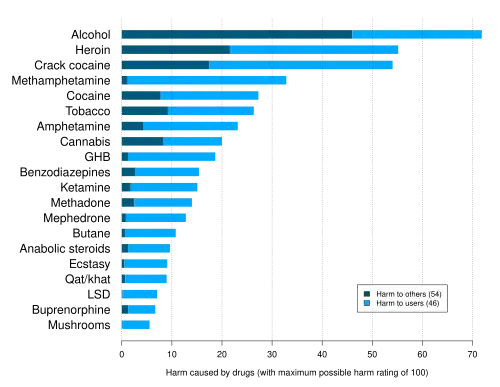

The addictive alkaloid nicotine is a stimulant, and popularly known as the most characteristic constituent of tobacco. In drug effect preference questionnaires, a rough indicator of addictive potential, nicotine scores almost as highly as opioids.[111] Users typically develop tolerance and dependence.[112][113] Nicotine is known to produce conditioned place preference, a sign of psychological enforcement value.[114] In one medical study, tobacco's overall harm to user and self was determined at three percent below cocaine, and 13 percent above amphetamines, ranking sixth most harmful of the 20 drugs assessed.[115]